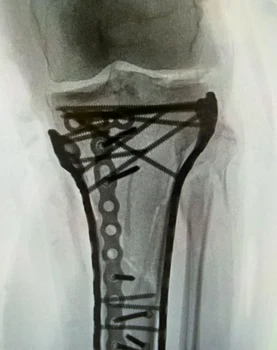

Imaginile publicate de Lindsey Vonn arată că a fost nevoie de o reconstrucție majoră pentru a-i stabiliza piciorul. Medicii au folosit o placă metalică lungă și aproximativ 20 de șuruburi, fixate în diferite unghiuri pentru a asigura suportul necesar.

„Am trecut cu bine de operație, a durat puțin peste 6 ore. După cum puteți vedea, a fost nevoie de o mulțime de plăcuțe și șuruburi pentru a pune totul la loc, dar Dr. Hackett a făcut o treabă incredibilă. Îi mulțumesc și Dr. Viola pentru asistența acordată în timpul intervenției!!